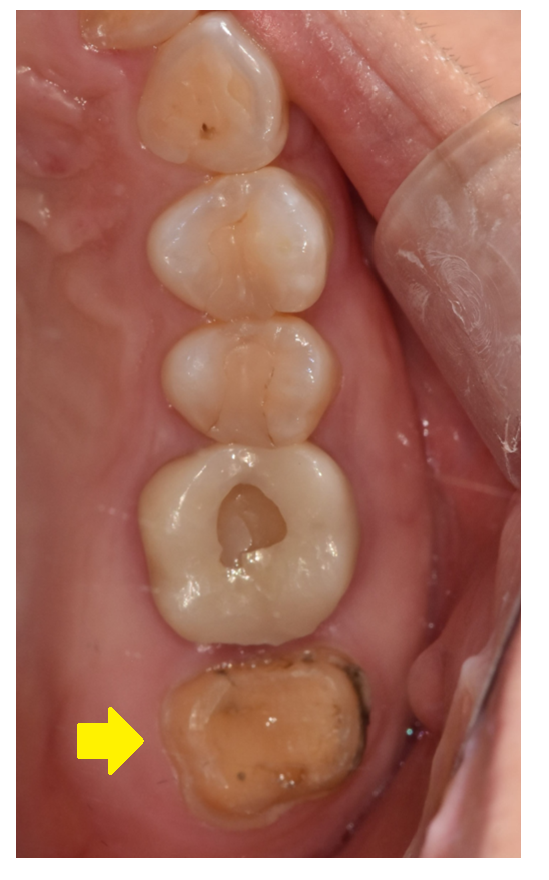

250725 충치가 일부만 있고 남아있는 치아가 건강한 경우

충치가 일부에만 있고

남아있는 치아가 건강할 경우

충치를 제거하고 다시 보철을 제작해주는

방법도 있죠.

250724 남아있는 치질이 거의 없는 경우